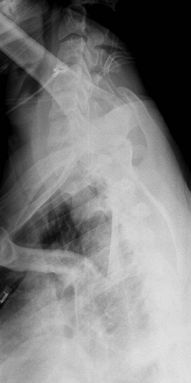

Thoracic Spine

Good initial assessment of pain and trauma. The lateral

view may need to be augmented by a swimmer’s view to show the

cervicothoracic junction.

![]() |

|

Figure 53 (A) AP thoracic spine. (B) Lateral thoracic spine.